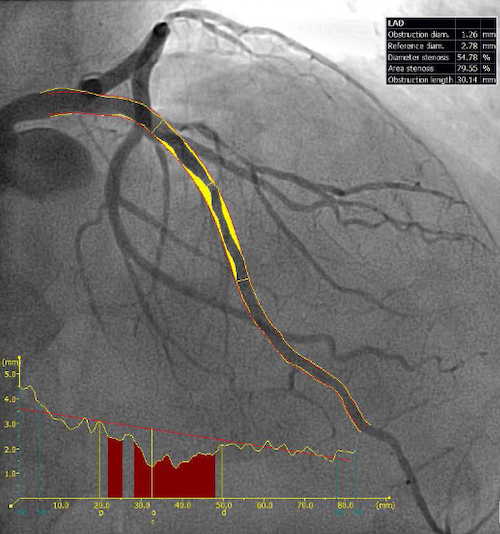

Major epicardial vessels with a percentage of DS (%DS) ≥20% were analyzed by visual assessment, QCA, and QFR. The severity of coronary artery stenosis was visually reported by trained interventional cardiologists from 20% to 90% on a scale of 10. QCA analysis was performed on the deidentified coronary angiograms by an experienced independent core laboratory (Yale Cardiovascular Research Group, New Haven). The trained analysts were blinded to the clinical records. Offline 2D-QCA was performed by QAngio XA, version 7.3 (Medis Medical Imaging System BV) to calculate reference vessel diameter, minimum lumen diameter, %DS, and lesion length based on standard protocol (Figure 1).

QFR was measured using the validated software, Medis Suite (Version 3.1, Medis Medical Imaging System BV). Detailed QFR methodology has been previously reported.18 In brief, the two best orthogonal angiographic views (at least 25° apart) of each vessel in the end-diastolic frame were used for 3D-QCA reconstructions. The reference vessel was constructed by fitting to healthy segments, preferably proximal and distal to the lesion of interest. Based on the manually selected reference points, the software generated a 3D-representation of the arterial lumen. QFR was then calculated using the frame count correction (Figure 1). Only vessels with two different angiographic views available were analyzed. As patients with LMCA stenosis were excluded from the study population, the LMCA was excluded from QCA and QFR measurement in the left coronary arteries. Based on previous validation, QFR ≤0.80 was considered the threshold to define functional ischemia.19